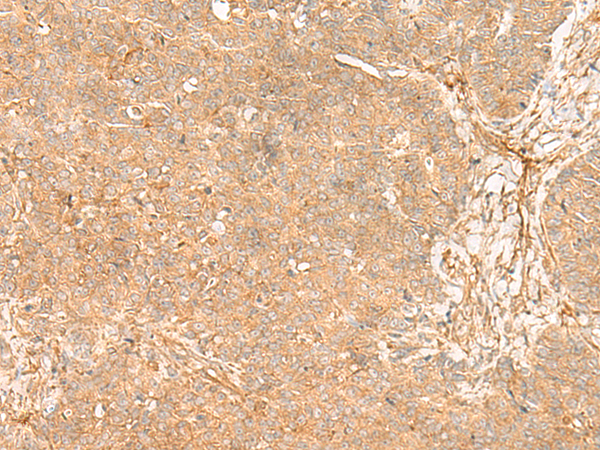

| IHC | 1/40-1/200 | Human,Mouse,Rat |

FLNC mutations are linked to myopathies (e.g., myofibrillar myopathy) and cardiomyopathies (e.g., hypertrophic or restrictive cardiomyopathy), often causing protein aggregation, sarcomere disruption, and impaired muscle function. FLNC antibodies are essential tools in research and diagnostics, enabling the detection of FLNC expression, localization, and pathological alterations via techniques like immunohistochemistry, Western blotting, and immunofluorescence.

Studies using FLNC antibodies have elucidated its role in disease mechanisms, including aberrant protein degradation and disrupted cytoskeletal signaling. Commercially available FLNC antibodies are validated for specificity, often targeting conserved regions (e.g., immunoglobulin-like domains). Their applications extend to evaluating tissue samples for FLNC-related pathologies and validating cellular models of FLNC dysfunction. Continued research aims to clarify FLNC's therapeutic potential in muscle disorders and its interplay with other sarcomeric proteins.